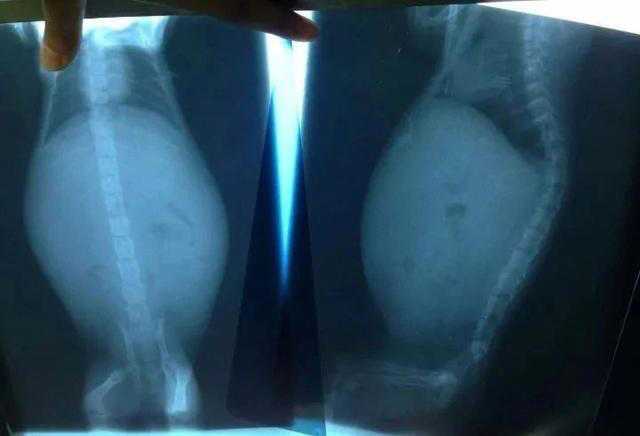

她的猫得了传腹,而且是干性。

她问过医生了,目前可以打411试试,全程下来1万块左右,甚至更多。而且治愈率只有70%,可能还会复发,并且有后遗症。

对阿良来说,这只猫拯救了他的精神世界,不是普通动物,就是他的亲人。后来他的猫也不幸得了传腹,但他兼职多打一份工,非常辛苦,所幸花了不到一万块就治好了。